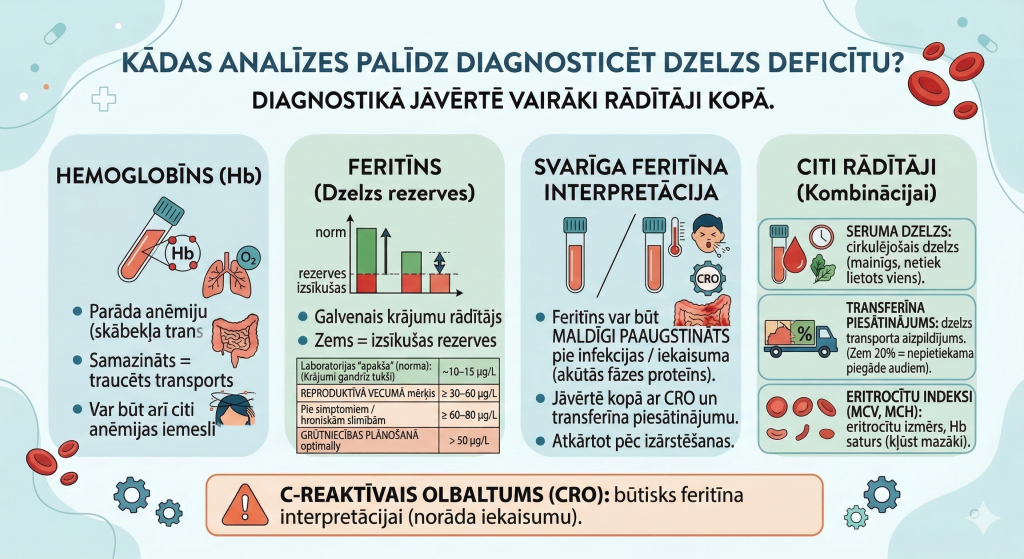

Kādas analīzes palīdz diagnosticēt dzelzs deficītu?

Dzelzs deficīta diagnostikā vienmēr jāvērtē vairāki laboratoriskie rādītāji kopā.

Hemoglobīns (Hb)

Hemoglobīns parāda, vai ir anēmija. Samazināts hemoglobīna līmenis nozīmē traucētu skābekļa transportu organismā.

Tomēr jāņem vērā, ka anēmijai var būt arī citi iemesli, tāpēc ar hemoglobīna analīzi vien nepietiek.

Feritīns – dzelzs rezervju rādītājs

Feritīns ir galvenais rādītājs, kas atspoguļo organisma dzelzs krājumus.

Zems feritīna līmenis parasti nozīmē, ka dzelzs rezerves organismā ir izsīkušas.

❗ Par laboratorijas normām un feritīna “apakšējo robežu”

Bieži pacienti saņem analīžu atbildi ar rezultātu “normas robežās”, tomēr praksē redzam, ka daudziem cilvēkiem, īpaši sievietēm, feritīna līmenis, kas laboratorijā vēl skaitās normāls, jau ir par zemu labas pašsajūtas nodrošināšanai.

Daudzās laboratorijās feritīna apakšējā norma ir ap 10–15 µg/L. Tomēr praktiski tas nozīmē, ka dzelzs rezerves ir gandrīz izsīkušas, pat ja hemoglobīns vēl ir normas robežās.

- Sievietēm reproduktīvā vecumā feritīna līmenim vēlams būt vismaz 30–60 µg/L,

- ja ir izteikti simptomi (nogurums, matu izkrišana, vājums) vai hroniskas slimības – mērķis bieži ir pat augstāks – ≥60–80 µg/L,

- grūtniecības plānošanas laikā optimāli – virs 50 µg/L.

Tāpēc ferritīna rādītāji vienmēr jāvērtē kopā ar pacienta sūdzībām, hemoglobīnu, iekaisuma marķieriem un kopējo klīnisko ainu.

Svarīgi zināt, ka akūtu infekciju un iekaisuma laikā feritīns var būt maldīgi paaugstināts, jo tas ir akūtās fāzes proteīns. Tas nozīmē, ka pat pie reāla dzelzs deficīta, feritīna vērtība var izskatīties normāla vai pat paaugstināta. Tāpēc šādās situācijās rezultāti vienmēr jāvērtē kopā ar citiem rādītājiem – CRO, transferīna piesātinājumu un klīnisko ainu, kā arī nepieciešamības gadījumā analīzes jāatkārto pēc akūtā iekaisuma procesa izārstēšanas.

Seruma dzelzs

Seruma dzelzs parāda, cik daudz dzelzs konkrētajā brīdī cirkulē asinīs. Šis rādītājs var svārstīties dienas laikā un ir jutīgs pret uzturu, tāpēc tas netiek izmantots viens pats diagnozes noteikšanai. Tomēr kombinācijā ar citiem rādītājiem tas palīdz izvērtēt dzelzs pieejamību organismā.

Transferīna piesātinājums

Transferīns ir proteīns, kas transportē dzelzi asinīs.

Transferīna piesātinājums parāda, cik liela daļa no šī transporta mehānisma ir aizpildīta ar dzelzi.

Ja piesātinājums ir zem 20 %, tas parasti liecina par nepietiekamu dzelzs piegādi audiem.

Eritrocītu indeksi (MCV, MCH)

Šie rādītāji parāda:

- eritrocītu izmēru

- hemoglobīna daudzumu eritrocītos

Pie ilgstoša dzelzs deficīta eritrocīti bieži kļūst mazāki un ar mazāku hemoglobīna saturu.

C-reaktīvais olbaltums (CRO)

CRO palīdz noteikt iekaisuma klātbūtni organismā un ir svarīgs feritīna interpretācijai.